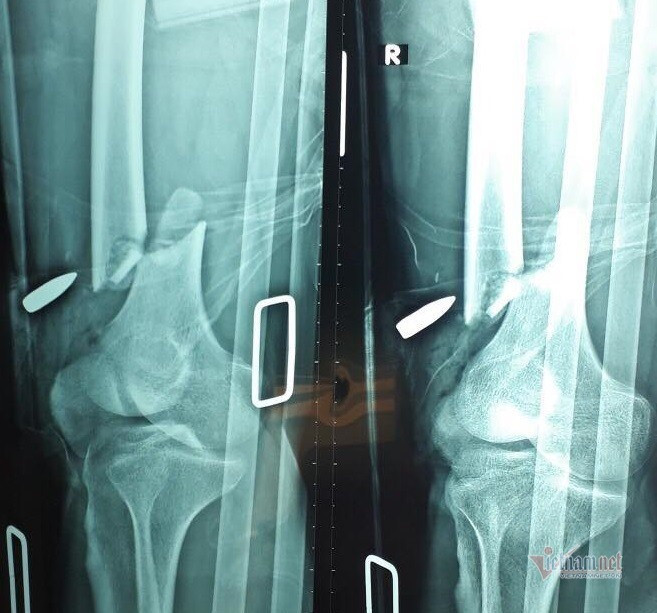

| Ảnh chụp X-quang cho thấy đầu đạn ghim vào đùi phải nạn nhân. Ảnh: Hòa Khánh |